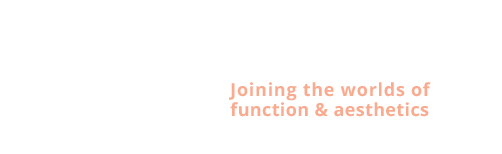

Bessina: "all on four " dentale implantaten

Behandeling tandheelkundige implantaten